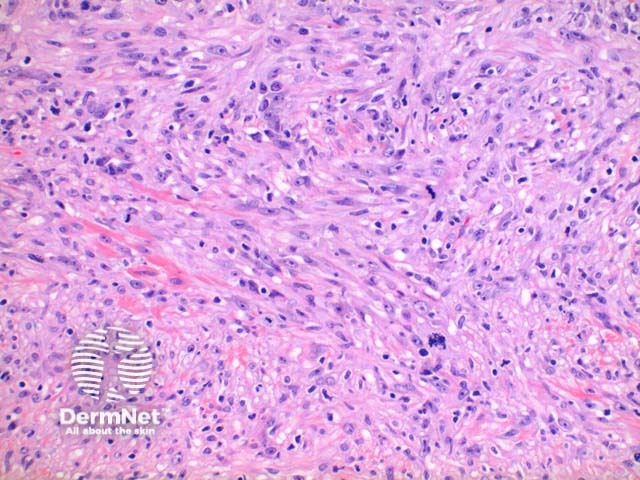

Scanning power view of histology of leiomyosarcoma shows a poorly circumscribed tumour nodule which may be dermal based in the less common dermal leiomyosarcoma (Figure 1) or deeply infiltrating in the subcutaneous form. The tumour is comprised of a spindle cell proliferation forming rough bundles and fascicles (Figures 2 and 3). High power demonstrates spindle cells with cigar shaped nuclei with prominent cytologic atypia and mitotic figures (Figures 4 and 5).

Figure 4